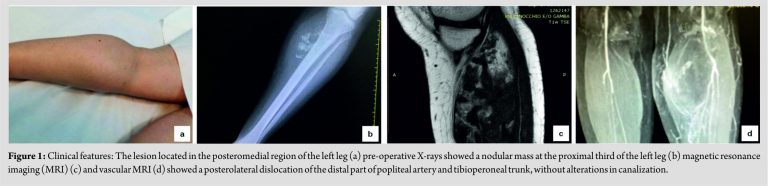

A 42-year-old woman presented at our observation with a 4-year history of a slow-growing, painful swelling on the posteromedial region of her left leg (Fig. 1a). X-rays evidenced the presence of a nodular mass at the proximal third of the left leg arising from the soft tissues next to the medial aspect of tibia (Fig. 1b); multiple calcific components were also observed. Subsequent magnetic resonance imaging (MRI) showed the presence of a 13 cm × 6 cm, 3 cm × 6 cm, 1 cm capsulated mass occupying soleus muscle, compressing, and displacing anteriorly gastrocnemius muscle (Fig. 1c). Moreover, the patient underwent vascular MRI of leg arteries which showed a posterolateral dislocation of the distal part of popliteal artery and tibioperoneal trunk (Fig. 1d), without alterations in canalization. Incisional biopsy was performed to assess the nature of the lesion. After the excision, specimens were immediately fixed in a 10% buffered formalin at room temperature for 48 h, cut into several tissue slices, and embedded in paraffin tissue blocks, as elsewhere reported [11,12]. Histologically, the bioptic samples consisted mainly of hyaline cartilage containing chondrocytes with chondrocytic lacunae; a diagnosis of a chondroma was suggested. However, to exclude the possibility of chondrosarcoma, which is a common differential diagnosis, especially when dealing with small biopsies, a surgical excision of the entire tumor, including the capsule, was performed (Fig. 2a). On the basis of radiological and histopathologic findings, a diagnosis of EC was made. At the present moment, 1 year after the surgical excision, the patient is in good general conditions and no local recurrence has been observed.